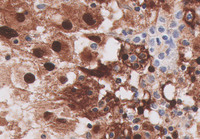

Figure 1-H&E

The low power H&E image demonstrates multifocal pale eosinophilic areas and higher power demonstrates that these pale areas comprise accumulations of large bland histiocytes with abundant pale eosinophilic cytoplasm with intermingled lymphocytes and plasma cells.  Higher power demonstrates that these histiocytes have small but distinct nucleoli.